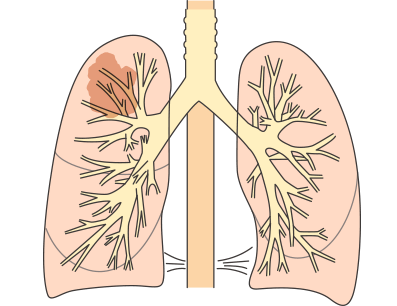

①肺がんの発生部位による違い

肺の入り口付近(肺門型肺がん):初期の段階から咳、痰や血痰などが発現します。

肺の奥(肺野型肺がん):初期に自覚症状はなく、進行して肺周囲の臓器に浸潤すると症状が現れます。

肺の中心にがんができる肺門型肺がんは、早期から咳や痰、血痰などの症状がでますが、肺の端のほうにがんができる肺野型肺がんでは初期症状はほとんどなく、進行期になって息切れや呼吸困難などがあらわれます。

肺がんと血痰の関係

肺がんはできた部位によって肺門型(肺の中心部にできたがん)、肺野型(肺の端にできたがん)に分けられ、型によって症状の出方が異なります。

肺門型の肺がんは気道に近い部位にでき、気道が刺激されるので、早期のうちから咳や喀痰、血痰があらわれることがあります。一方、肺野型の肺がんは気道から遠い部位にできるので、多くの場合、進行するまでは血痰はあらわれにくく、無症状で経過します。術後に血痰がでた場合は再発が疑われます。

その他、肺がんはがんの発生部位によって肺門型肺がんと肺野型肺がんに分けられます。

発生部位による分類

| 特徴 | |

|---|---|

| 肺門型肺がん |

|

| 肺野型肺がん |

|

肺門型肺がんと肺野型肺がん